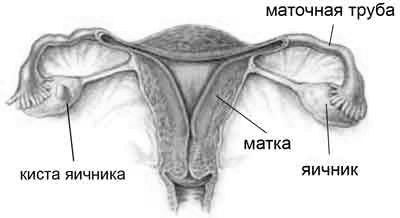

Рідина в яєчниках у жінок: -

Як лікувати кісту яєчника і можна-

Лапаротомія кісти яєчника: -